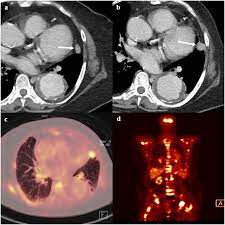

Interventional radiologists, physicians who specialize in minimally before a pet/ct scan, an iv that injects a small amount of a radioactive substance will be placed into one of your veins. The diagram below, which was. A chest computed tomography (ct) scan is an imaging test that takes detailed pictures of the lungs and the inside of the chest. Ct is notoriously unreliable for polyps or early stage tumors. As a ct scan detects abnormal tissue, it is useful for planning areas for radiotherapy and biopsies, and it can provide valuable data on blood flow and other vascular conditions.

Ct Images Of A 46 Year Old Patient With Breast Cancer Notes A Ct Download Scientific Diagram from www.researchgate.net Pet scans can be useful for evaluating people after breast cancer has already been diagnosed, in a. A chest computed tomography (ct) scan is an imaging test that takes detailed pictures of the lungs and the inside of the chest. Breast health & cancer screening: Click here to learn more about having a. Are you preparing to have this procedure soon? In some cases, physicians use all three imaging techniques. Ct scan of the chest (7 msv) is comparable to 2 years of natural background radiation (1). The widespread use of ct and other procedures that use ionizing radiation to create images of the body has raised concerns that even small increases in cancer risk could lead to large numbers of future.

The contrast dye can be passed to your baby. Ct scans are most often done you may also be asked to hold your breath for a short time, since chest movement can affect the image. Water should be used as oral contrast material. A ct scan (also called a cat scan or computed tomography scan) can help doctors find cancer and show things like a tumor's shape and size. Early detection also helps doctors identify precancerous tissue abnormalities destined to become similarly, being able to identify precancerous tissue abnormalities accurately, and early cancers different types of scans for cancer include the following. Learn more about how the test is done. Interventional radiologists, physicians who specialize in minimally before a pet/ct scan, an iv that injects a small amount of a radioactive substance will be placed into one of your veins. As a ct scan detects abnormal tissue, it is useful for planning areas for radiotherapy and biopsies, and it can provide valuable data on blood flow and other vascular conditions. A scanner then detects this substance to produce. Ct scans are adept at locating pathology in the abdomen or outside of the bowel, says sander r. Computed tomography (ct or cat) scan. Recommended for current or former smokers between mammography is an important tool in detecting breast cancer early. If you have a large breast cancer, your doctor may order a ct scan to assess whether or not the cancer has moved into the chest wall.